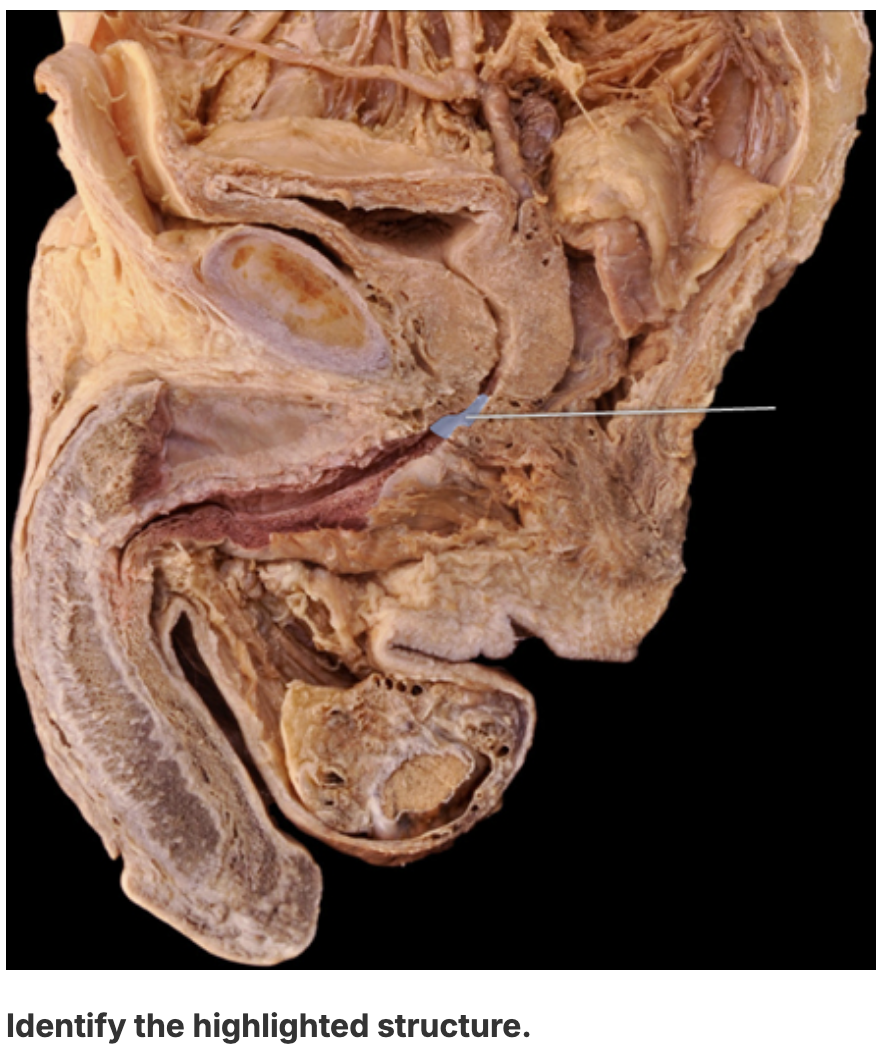

ejaculatory duct